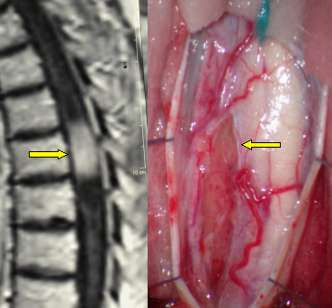

Sintomi, Segni e Complicazioni. Terapia, Prognosi e Prevenzione. Un nodulo polmonare è una formazione anomala, generalmente isolata, rotonda oppure ovale, che ha sede d’origine su uno dei due polmoni. Se il tumore al polmone ha dato origine a metastasi in altre parti dell’organismo, la terapia locale può essere usata per tenere sotto controllo la malattia nelle specifiche zone colpite.

Ad esempio, se il tumore al polmone ha formato metastasi al cervello , può essere tenuto sotto controllo con la radioterapia alla testa. Le metastasi al cervello , i tumori intracranici più comuni negli adulti, sono volte più frequenti dei tumori cerebrali primari. La metastasi può svilupparsi in una sola parte del cervello o interessare più parti contemporaneamente.